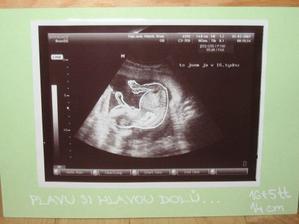

SRPŇÁTKA 2007 - fotky UTZ

album věnované mimískům, které se narodí v srpnu 2007 a jejich maminkám ze "Společného termínu SRPEN"